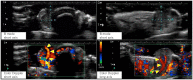

Figure 2.

Ultrasound findings. B-mode images revealed a well-defined hypoechoic region seen protruding from the subcutis to the outside of the body. Color doppler images showed pulsatile vascular inflow from deep within the lesion (arrowhead).